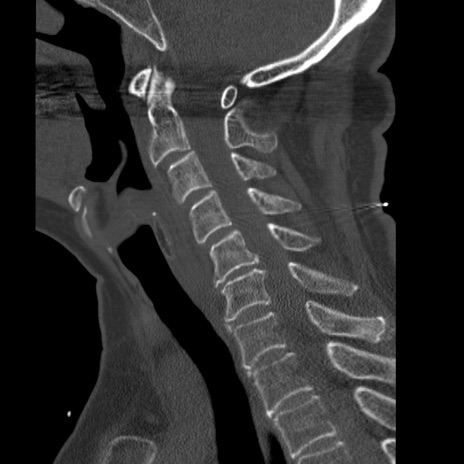

症例50 頚椎CT(矢状断像)

【症例】60歳代女性

【主訴】後頭部〜右後頸部にかけての痛み

【現病歴】本日飲食店でコーヒーを飲んでいたところ、突然後頭部〜右後頸部にかけて痛みが出現し、右上肢の感覚障害を伴ったため救急要請。

【身体所見】脳神経学的に明らかな異常所見を認めず。右上肢に軽度の感覚障害あり。

異常所見と診断は?

頚椎CT